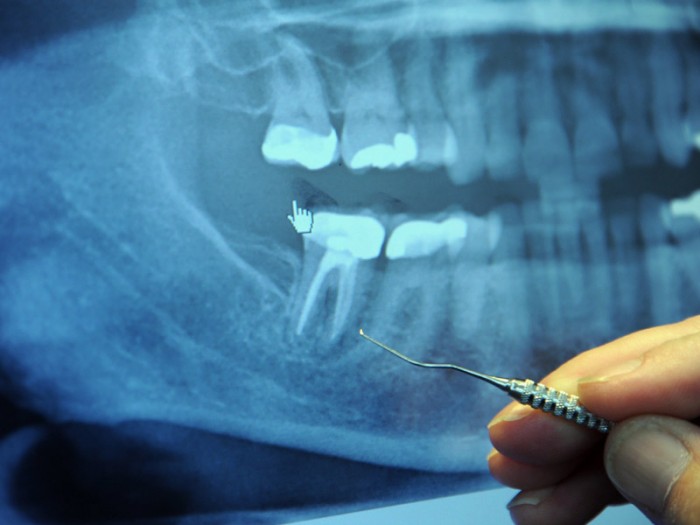

Корневой канал

В США ежегодно лечат 25 миллионов зубных корневых каналов.

Зубы, которые расположены в таких корневых каналах, являются «мертвыми» и могут накапливать токсичные анаэробные бактерии, которые, при определенных условиях, могут попасть в кровь и стать причиной ряда серьезных заболеваний, которые могут не проявлять себя в течение десятилетий.

Когда дантист лечит корневой канал, он делает полость в зубе, затем заполняет дырку веществом, которое называется гуттаперча. Оно блокирует поставку крови в зуб. Исходя из этого, жидкость больше не способна циркулировать через зуб. Но лабиринт из крошечных туннелей остается. И бактерии, которые не получают питательных веществ, начинают прятаться в этих туннелях, где они находятся в полной безопасности от антибиотиков и от иммунной системы.